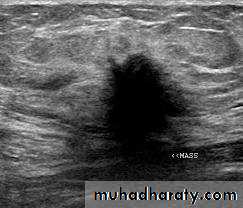

(2)ultrasound: ultrasound is particularly useful in young women with dense breasts in whom mammograms are difficult to interprets, and in distinguishing cysts from solid lesions. It also can be used to localize impalpable areas of breast pathology. It is useful as screening tool and remains operator dependent. Increasingly, ultrasound of the axillary tissue is performed when cancer is diagnosed and guided percutaneous biopsy of any suspicious glands may be performed.